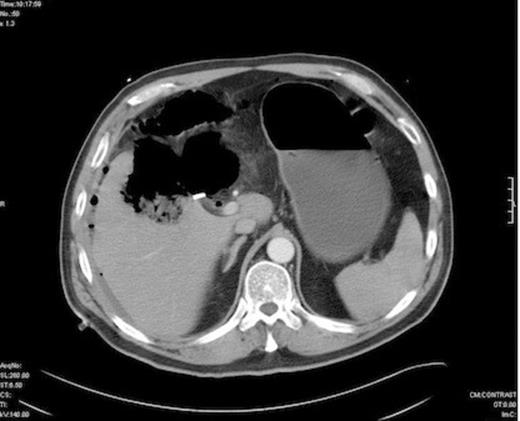

Initial treatment comprised intravenous fluid resuscitation, high flow oxygen and broad spectrum antibiotics (Tazocin, Gentamicin and Metronidazole). He proceeded to CT scan which demonstrated a gas filled cavity in and under the right lobe of liver. A laparotomy was performed, revealing a large abscess cavity in the right lobe of liver emanating from the gallbladder fossa. This contained pockets of gas. The bile duct was found intact and the cystic duct clips secure. The pus was drained and a generous peritoneal lavage performed. Large bore (32Fr) sub-hepatic and sub-phrenic drains were placed.

CT at re-admission 1 week post lap chole - Free intraperitoneal gas abscess in gallbladder fossa